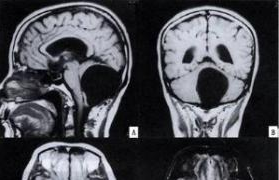

1. 颅脑CT平扫+增强示小脑蚓部低密度影,考虑占位性病变,建议MR检查。

2. 颅脑MR平扫+增强示颅脑MR平扫+增强示小脑蚓部异常信号影,考虑囊肿伴梗阻性脑积水。